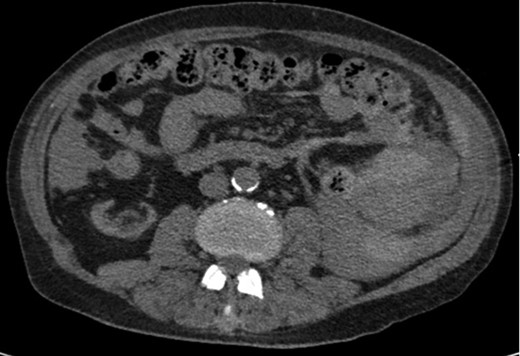

A 68-year-old male with history of living donor renal transplant presented to the ED with acute onset of profound weakness, fatigue, left upper quadrant abdominal pain, hypotension and lactic acidosis. On exam, he exhibited mild left upper quadrant and epigastric tenderness without evidence of peritonitis. CT imaging demonstrated splenomegaly with a large splenic hematoma measuring 15.7 × 9.2 × 12 cm and associated hemoperitoneum (Figs 1–3). In addition, innumerable osseous lytic lesions were identified. Given these findings, emergent surgical consultation was obtained and his coagulopathy reversed. He remained hypotensive despite resuscitation, thus was taken for laparotomy. Upon abdominal entry, a large amount of old clot was evacuated. The abdomen was packed in all quadrants in the standard fashion. Upon removal of the left upper quadrant packs, active hemorrhage began to well from the region of the spleen which was mobilized and removed via splenectomy. Upon gross inspection, the spleen was hyperemic and abnormally indurated, with an avulsion type injury extending several centimeters across the inferior pole. There was no evidence of pseudoaneurysm or other gross pathology. Given the patient was mildly hypothermic and coagulopathic with continued oozing from the retroperitoneum, the decision was made to pack the splenic fossa and place a temporary wound vac. The patient was transported to the ICU for resuscitation and brought back to the OR the next morning for re-exploration and closure. Despite hemodynamic stabilization, he underwent a prolonged hospitalization complicated by atrial fibrillation, renal allograft failure, VAP, and ultimately PEA arrest progressing to asystole. He died 6 weeks following splenectomy. The pathology from the spleen revealed splenomegaly with parenchyma that was replaced with amorphous and acellular eosinophilic material. Histologic staining (Thioflavin-T) was positive for amyloidosis, AL-type. Oncology was consulted based on these findings with concern for lymphoproliferative disorder given osseous findings on CT, splenic pathology, and history of immunosuppression. Bone marrow biopsy was subsequently obtained which showed more than 50% atypical plasma cells/plasma blasts (CD138+; PAX5 negative; EBV (EBER) negative) and no amyloidosis, consistent with multiple myeloma. Urine showed Bence-Jones protein. Serum immunofixation studies were remarkable for a monoclonal IgG lambda gammopathy, consistent with the diagnosis of AL amyloidosis associated with systemic myeloma.

Axial CT imaging of the pelvis demonstrating heterogeneous fluid (blood) in the pelvic small bowel mesentery. Also shown is the patient’s renal transplant with clear perinephric fat planes. The renal graft was grossly uninvolved and viable appearing at the time of laparotomy.